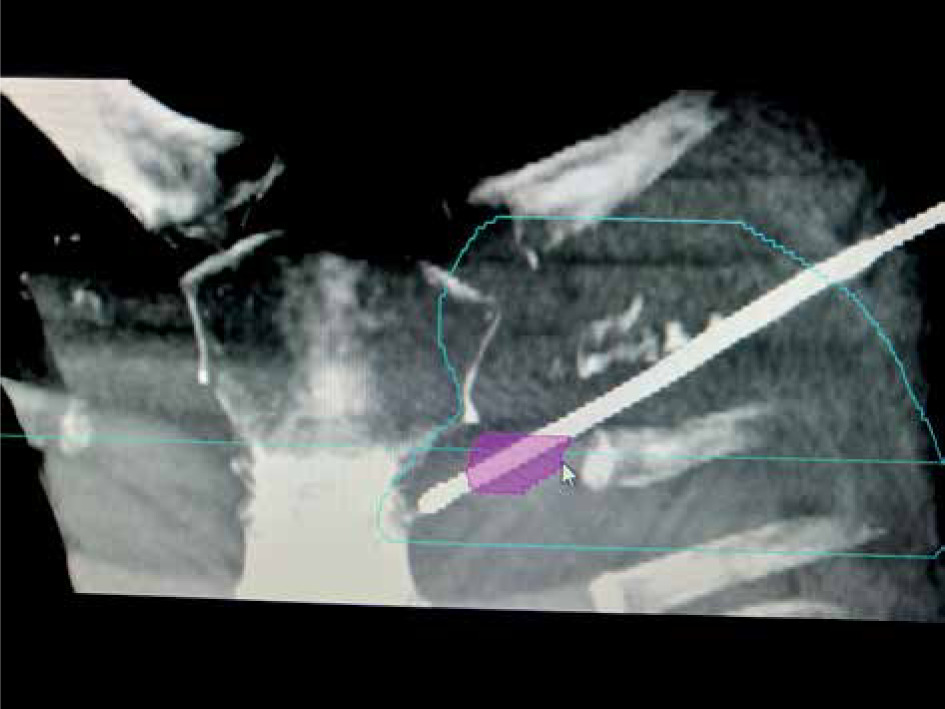

Advanced Liver and Lung Brachytherapy Treatment Setup

Lungs / Liver Cancer Brachytherapy

We provide cutting-edge brachytherapy for both primary and metastatic lung and liver cancers. Our advanced techniques ensure precise radiation delivery, improving treatment outcomes while reducing side effects for patients in Nepal. Learn More